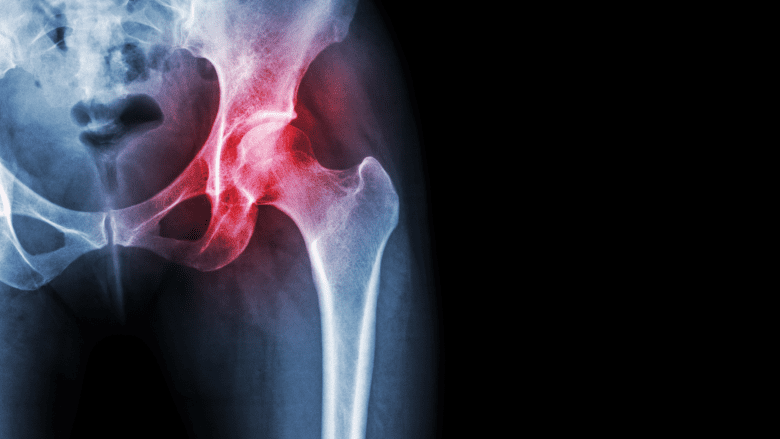

The most common hip bursitis symptoms are pain and tenderness around the outside of the hip